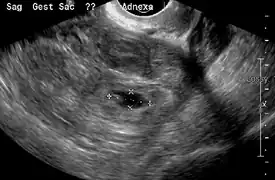

An ultrasound showing a gestational sac with fetal heart in the fallopian tube has a very high specificity of ectopic pregnancy. It involves a long, thin transducer, covered with the conducting gel and a plastic/latex sheath and inserted into the vagina.[32] Transvaginal ultrasonography has a sensitivity of at least 90% for ectopic pregnancy.[5] The diagnostic ultrasonographic finding in ectopic pregnancy is an adnexal mass that moves separately from the ovary. In around 60% of cases, it is an inhomogeneous or a noncystic adnexal mass sometimes known as the "blob sign". It is generally spherical, but a more tubular appearance may be seen in case of hematosalpinx. This sign has been estimated to have a sensitivity of 84% and specificity of 99% in diagnosing ectopic pregnancy.[5] In the study estimating these values, the blob sign had a positive predictive value of 96% and a negative predictive value of 95%.[5] The visualization of an empty extrauterine gestational sac is sometimes known as the "bagel sign", and is present in around 20% of cases.[5] In another 20% of cases, there is visualization of a gestational sac containing a yolk sac or an embryo.[5] Ectopic pregnancies where there is visualization of cardiac activity are sometimes termed "viable ectopic".[5]

Transvaginal ultrasonography of an ectopic pregnancy, showing the field of view in the following image

Ultrasound image showing an ectopic pregnancy where a gestational sac and fetus has been formed